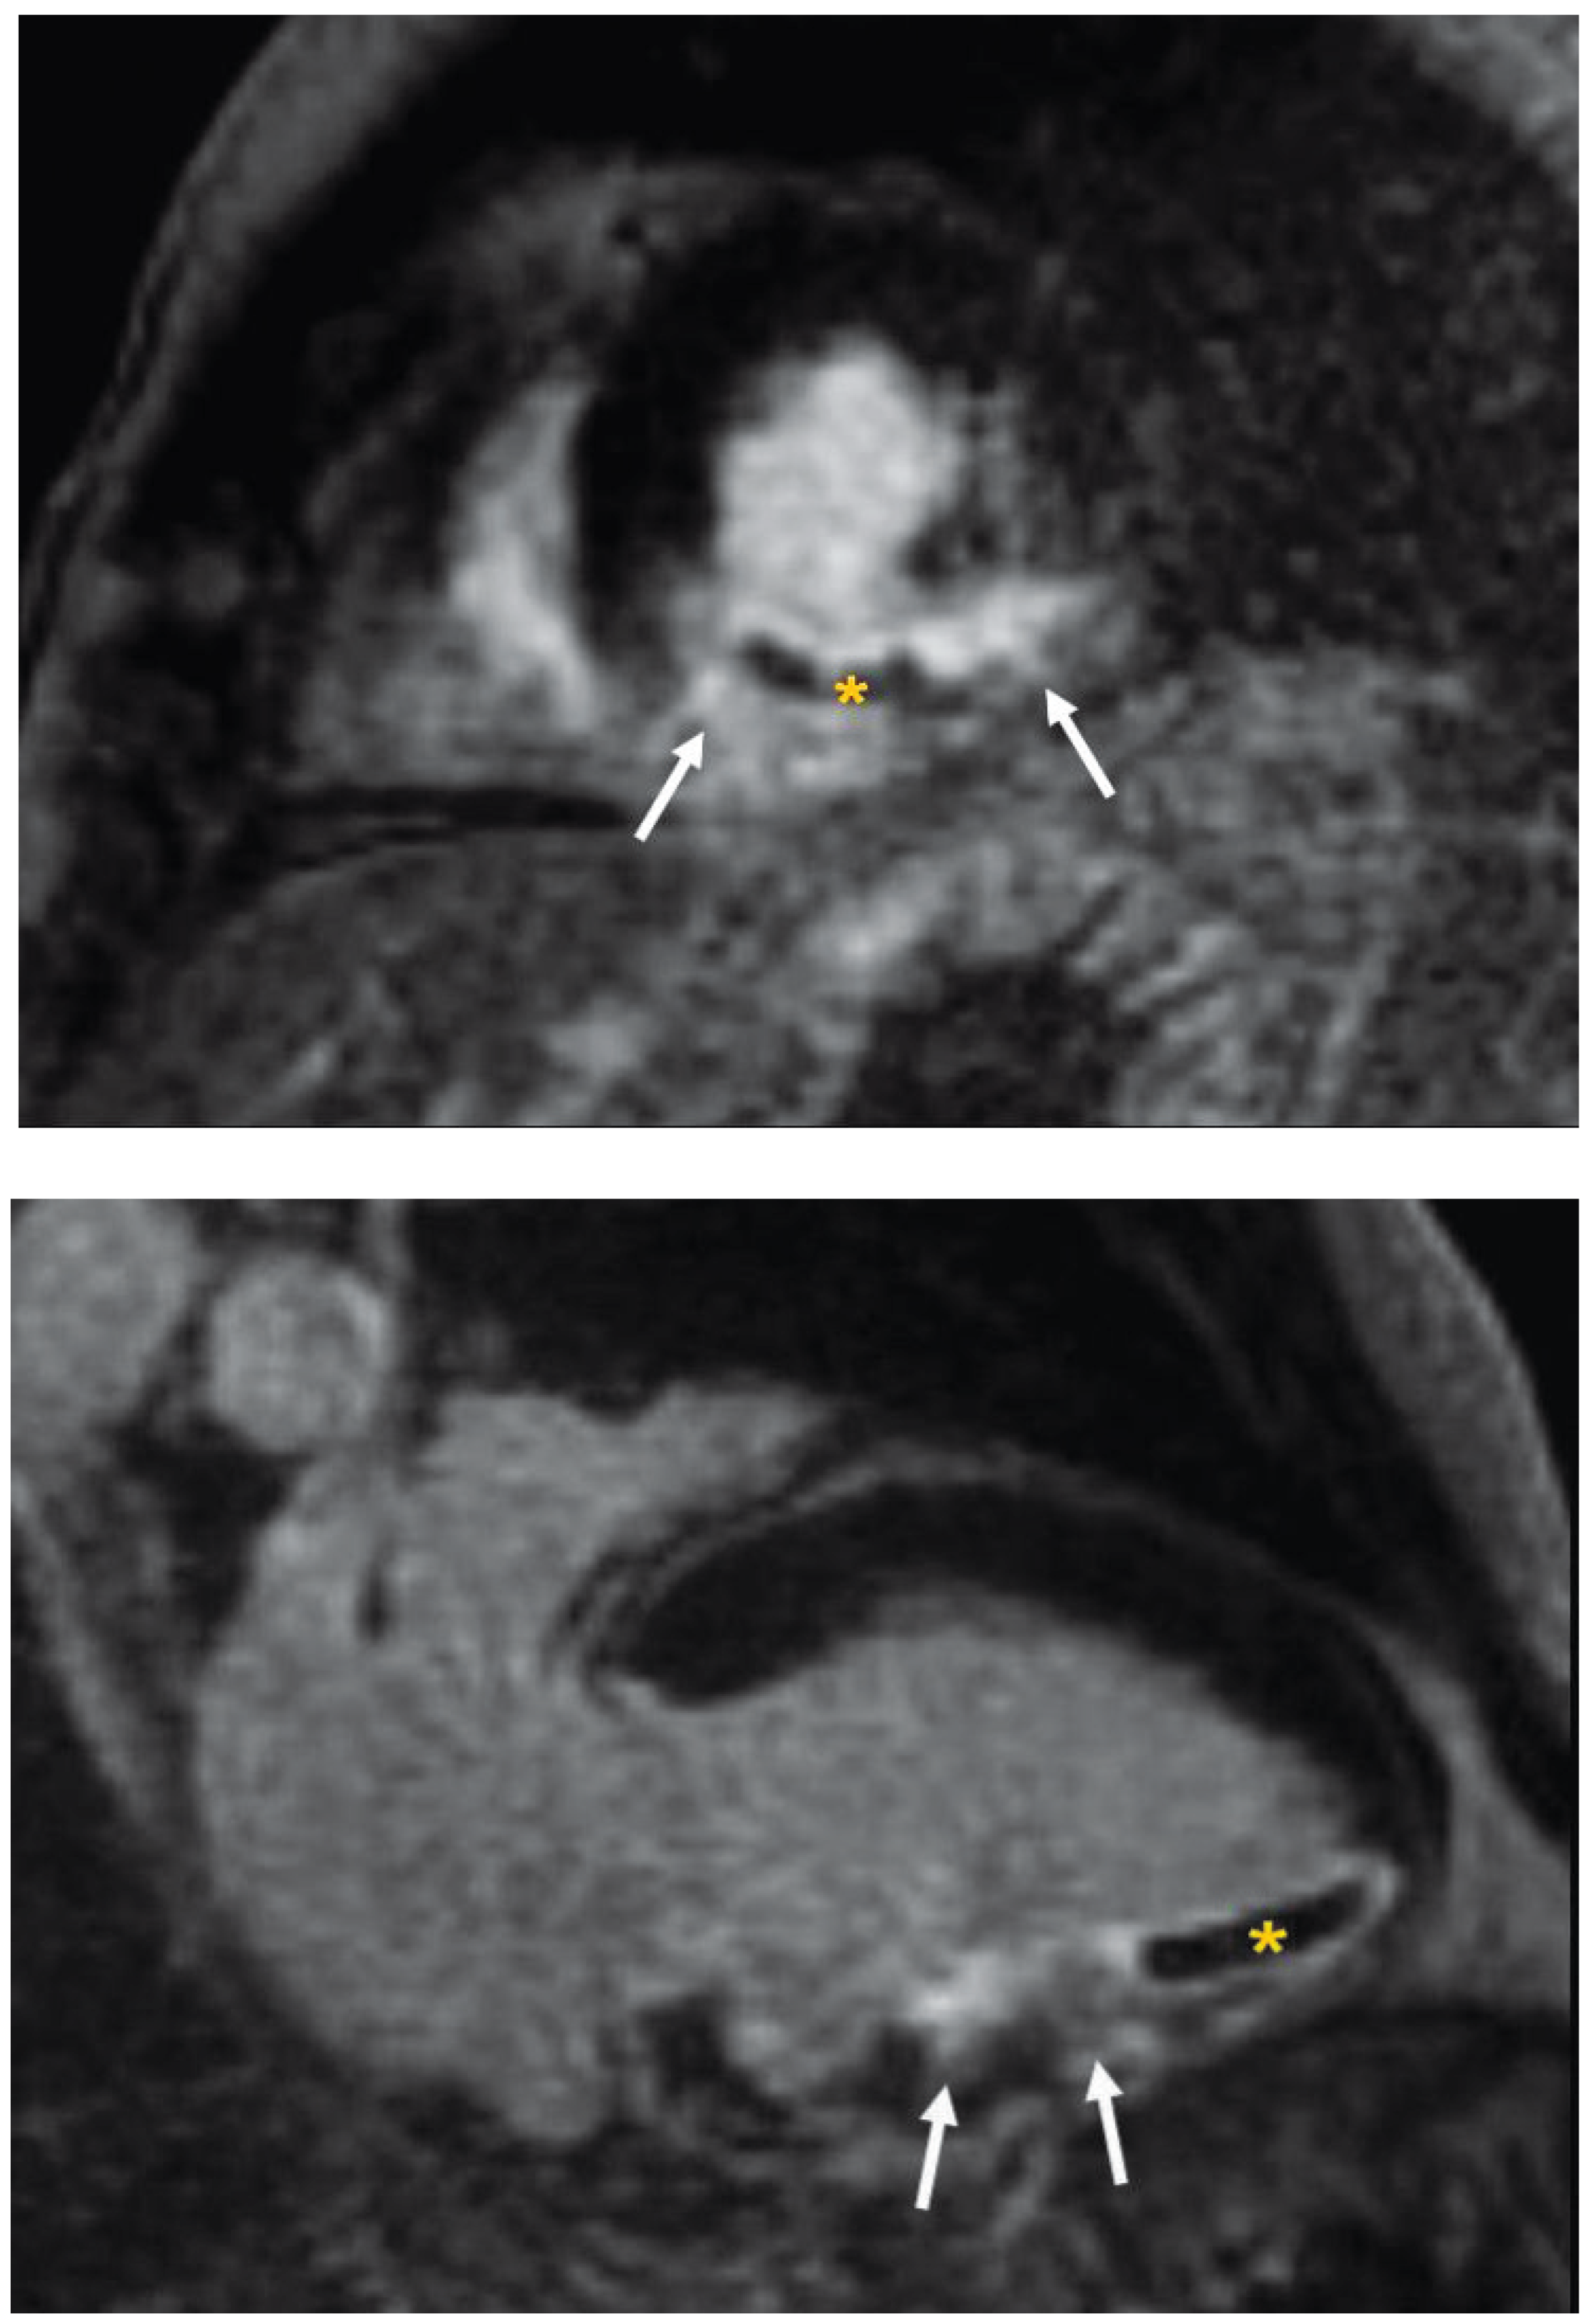

Three days after the emergent PCI cardiac magnetic resonance (CMR) imaging was performed on a clinical 1.5 Tesla scanner using a dedicated 8-element phased array cardiac coil. Cine imaging with steady state free precession gradient echo revealed overall normal systolic function of a mildly dilated left ventricle with only mild regional hypokinesis of the mid to distal inferior wall. T

2-weighted CMR was performed in the cardiac short-axis direction using dark-blood T

2-weighted STIR fast-spin echo, revealing an elevated signal intensity in the inferior segments extending to the inferolateral and inferoseptal walls, with right ventricular involvement consistent with tissue oedema. There was a central core of hypointense signal suggestive of intramyocardial haemorrhage (

Figure 1) Also, T